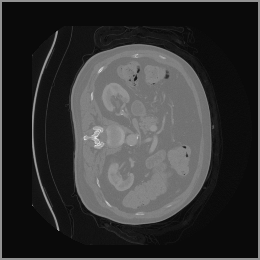

To demonstrate the advantages of 3D semantic image synthesis over 2D semantic semantic image synthesis, we conducted a detailed comparison with the SegGuidedDiff [26] model. SegGuidedDiff generates medical images based on 2D semantic maps, producing individual 2D slices that are later stacked to form a 3D image. However, this approach has limitations in capturing spatial continuity and coherence across slices, which is critical for representing the spatial structure of 3D medical images. As a result, inconsistencies often arise between different slices, particularly in preserving anatomical structures across the coronal and sagittal planes. The generated images exhibit varying levels of denoising, resulting in differences in brightness and sharpness across the images. This inconsistency in denoising can lead to noticeable variations in visual quality, where some regions appear clearer and others less distinct.

As shown in Figure 5, the generated slices exhibit high consistency across adjacent slices. The anatomical structures and semantic patterns are smoothly and coherently preserved between slices, indicating that our model is capable of generating 3D-consistent synthetic images rather than isolated 2D slices.

In contrast, the segmentation result of synthetic data generated by SegGuidedDiff using 2D semantic map slices shows significantly lower performance (Dice = 0.602). Notably, SegGuidedDiff generates images slice-by-slice in 2D without modeling the full 3D spatial context. As a result, the synthesized volumes often suffer from inter-slice inconsistencies and unrealistic spatial structures, which negatively impact the downstream segmentation performance.

Figure 8 further supports these findings: the images generated by Med-LSDM preserve spatial coherence across coronal and sagittal planes, whereas those from SegGuidedDiff show noticeable inconsistencies. These artifacts likely result from the 2D nature of SegGuidedDiff, which fails to account for 3D spatial relationships. In contrast, our model’s volumetric diffusion framework inherently preserves anatomical consistency, highlighting its advanta in synthesizing high-fidelity 3D medical images.